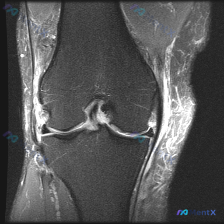

膝关节MRI读片讨论:外侧半月板异常,这个周围高信号你会漏吗?

最近看到这份膝关节MRI T2冠状位的病例资料,核心问题是半月板异常,整理了完整的读片思路和大家分享。

本次提供的是膝关节MRI T2序列冠状位图像,核心观察结果如下:

- 内侧半月板: 体部结构可见,内部没有明显贯穿关节面的高信号,仅边缘形态略不规则

- 外侧半月板: 体部实质内可见明确高信号,且信号直接延伸至关节面,是明确的异常表现

- 外侧周围软组织: 外侧半月板旁、外侧关节间隙区域可见弥漫性异常高信号,边界相对模糊

- 其他结构: 股骨远端、胫骨近端骨皮质连续,没有大范围骨水肿或骨折;内侧副韧带无明显异常,外侧副韧带区域信号杂乱;关节腔内可见少量液体信号